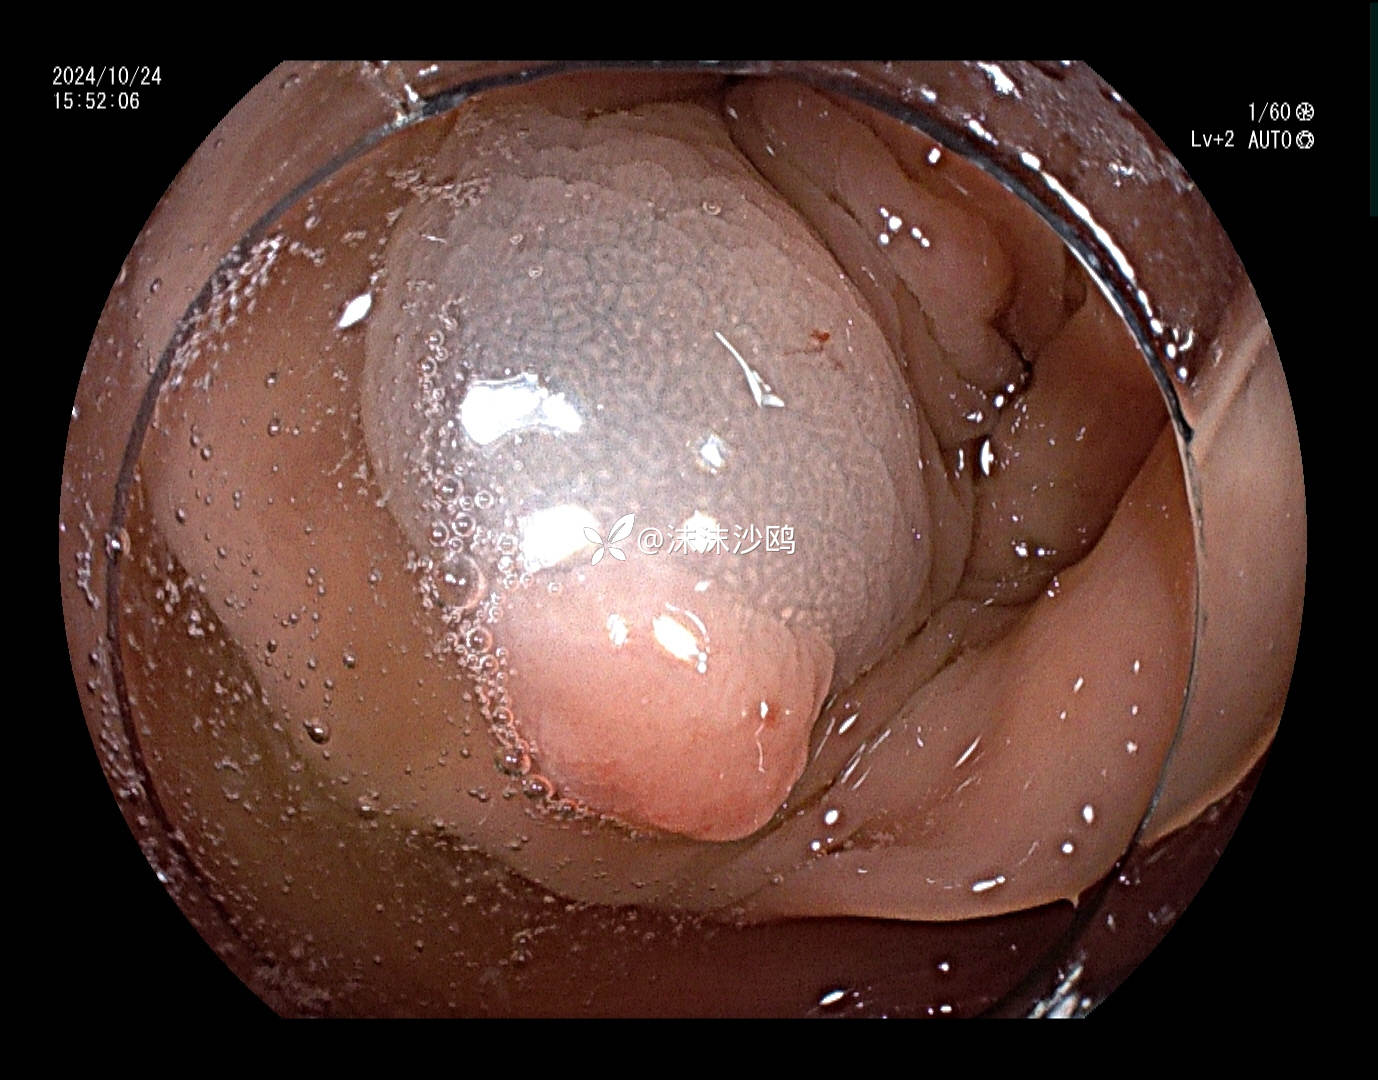

患者去年发现乙状结肠肿瘤同是发现多发腺瘤样隆起,先做了肿瘤切除手术,没有进一步放化疗,现来复查肠镜顺便嘎息肉。翻看之前的肠镜报告,肠道清洁差,发现的息肉就有六七个,应该还有漏掉的。嘱患者肠道一定要清洁到位。今日下午只安排了他一个人的肠镜专场,专门处理他的息肉。

冰山一角,大大小小嘎了十三四个,大的就有六七个,大部分EMR切除。希望术后不要有并发症。